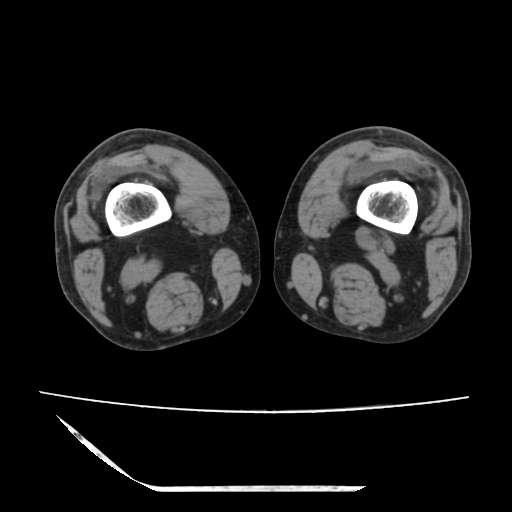

标题: CT13225:老年男性,左膝关节疼痛数月;请各位老师讨论。 [打印本页]

标题: CT13225:老年男性,左膝关节疼痛数月;请各位老师讨论。

骨质增生,骨性关节面硬化,关节积液,考虑退行性骨关节病

关节腔内少量积液,关节面退变。

双膝退变

骨质增生,骨性关节面硬化,关节间隙失常,关节积液,考虑退行性骨关节病.

骨质增生,骨性关节面硬化,关节积液,考虑退行性骨关节病。

这个病例诊断:退行性骨关节炎